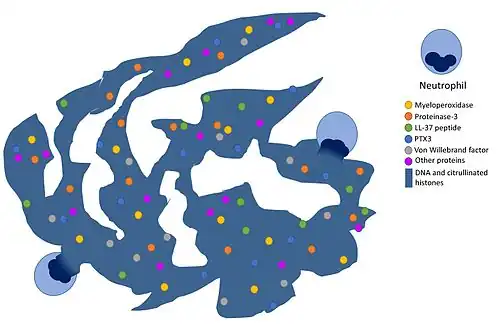

Ещё одна форма противомикробной активности нейтрофилов заключается в особом типе программируемой клеточной гибели, характерном для нейтрофилов, — нетозе[41]. При нетозе погибающий нейтрофил выбрасывает свою ДНК наружу в виде так называемых внеклеточных ловушек нейтрофилов (от англ. neutrophil extracellular traps, NETs). Внеклеточные ловушки нейтрофилов состоят из хроматина и сериновых протеаз и способны иммобилизовать и убивать микробные клетки[42]. Таким образом, внеклеточные ловушки нейтрофилов также противодействуют распространению клеток патогенов по тканям. При сепсисе массовый нетоз происходит непосредственно в кровеносных сосудах[43]. Образование внеклеточных ловушек нейтрофилов может вносить вклад в развитие ряда воспалительных заболеваний, таких как преэклампсия[44], а их образование в кровеносных сосудов может приводить к формированию тромбов, в том числе в коронарных артериях[45][46]. В 2018 году было показано, что один и тот же нейтрофил может подвергаться и апоптозу, и нетозу одновременно; этот вид программируемой клеточной гибели нейтрофилов получил название апонетоз[47].